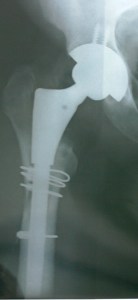

Earl’s Revised Right Hip – Zimmer Ceramic on Ceramic – done Sept 2011; Removed S&N Birmingham Spectrum THR (MoM)